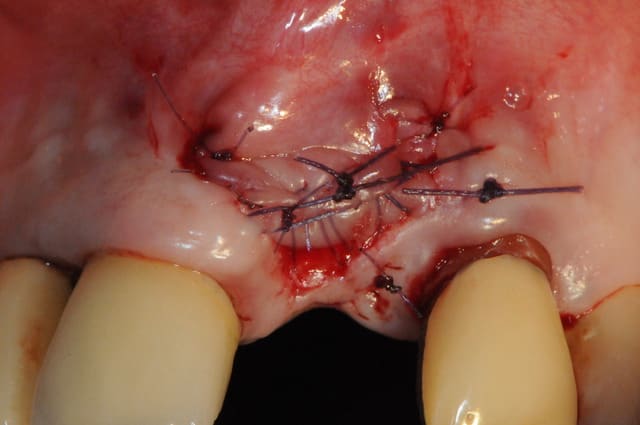

Le cas EII sur 12

positionnement de l'implant en ménageant un espace en vestibulaire qui st comblé avec de l'os synthétique car l'espace est important et il y a une perforation de la corticale vestibulaire en regard de l'apex de la dent.

pour recouvrir tout cela et gagner un peu de volume vestibulaire

un lambeau palatin pédiculé qui après une rotation va recouvrir l'implant et la greffe.